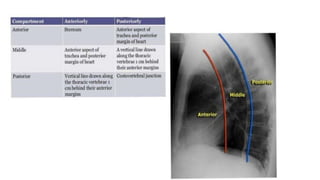

Mediastinum

• The trachea should be centrally located or slightly to the right

• The aortic arch is the first convexity on the left side of the

• The pulmonary artery is the next convexity on the left, and the

branches should be traceable as it fans out through the lungs

• The lateral margin of the superior vena cava lies above the right heart

border

Mediastinum • The tracheashould be centrally located or slightly to the right • The aortic arch is the first convexity on the left side of the mediastinum • The pulmonary artery is the next convexity on the left, and the branches should be traceable as it fans out through the lungs • The lateral margin of the superior vena cava lies above the right heart border